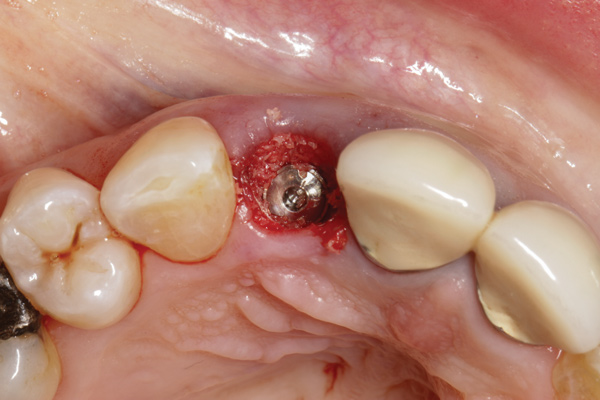

Fig 5. Atraumatic extraction without raising the flap, with the intention of minimizing bone loss, especially in the interproximal area.

Figure 5